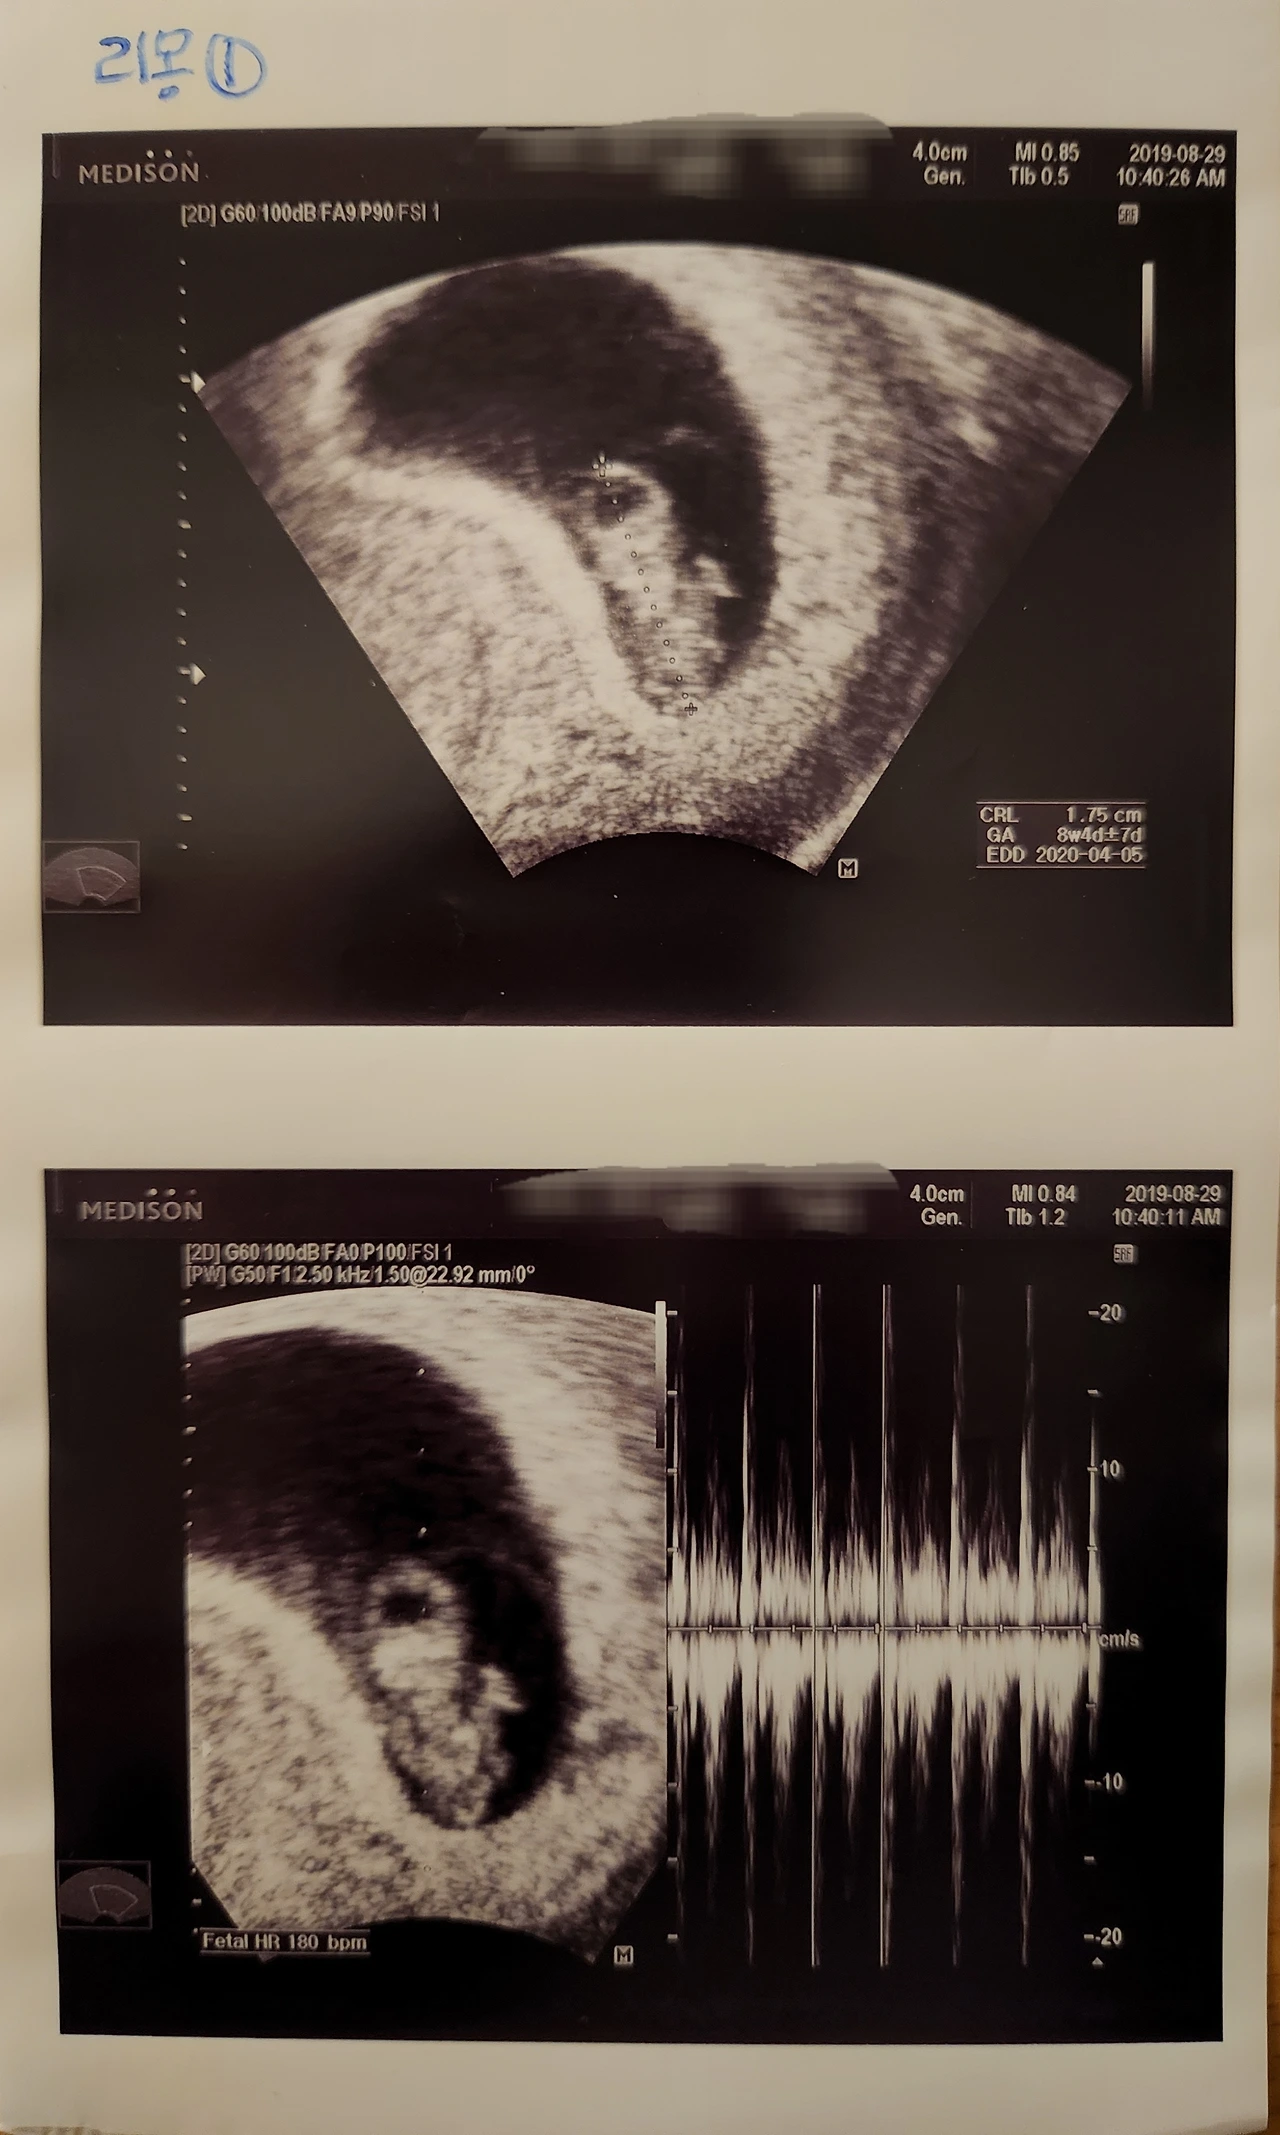

심장이 뛰지 않는데도 초음파 화면 속 양수에서 아무 일도 없다는 듯이 흔들리는 내 첫 번째 아기를 보고 영화 그래비티에서 고요한 우주를 홀로 정처 없이 유영하는 조지 클루니가 생각났다.

의사 선생님은 이미 프린트된 그날의 초음파 사진을 주지 않으려고 했지만 나는 내 첫 번째 아기가 '잊히는 존재'가 아니라 '누군가가 기억해주는 존재'를 만들어주고 싶어서 받아왔고 집에서 그 사진을 끌어안고 하염없이 울다.

둘째이자 태어나기로는 첫째를 임신했을 때 특히 9주까지는 아기가 어떻게 될까 매번 산부인과 검진 시 "심장은 뛰나요?"를 나도 모르게 가장 먼저 물어봤더랬다.